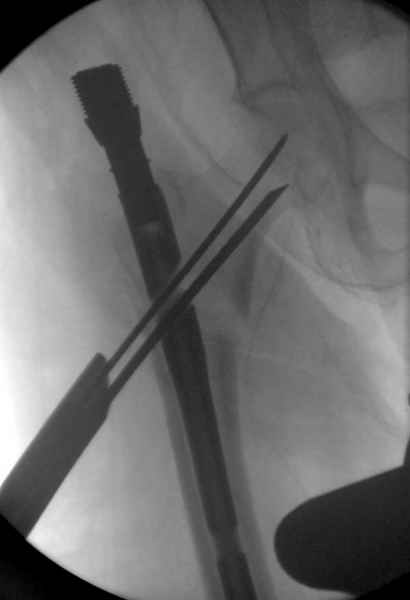

В общем, сделали. См. приложение.

Длина и из-за этого ось получились не совсем такие, как хотелось бы, все-таки срок после той операции уже 6 недель. Может быть, стоило провести дистракцию аппаратом неделю-другую. Заранее спасибо за комментарии и критику.